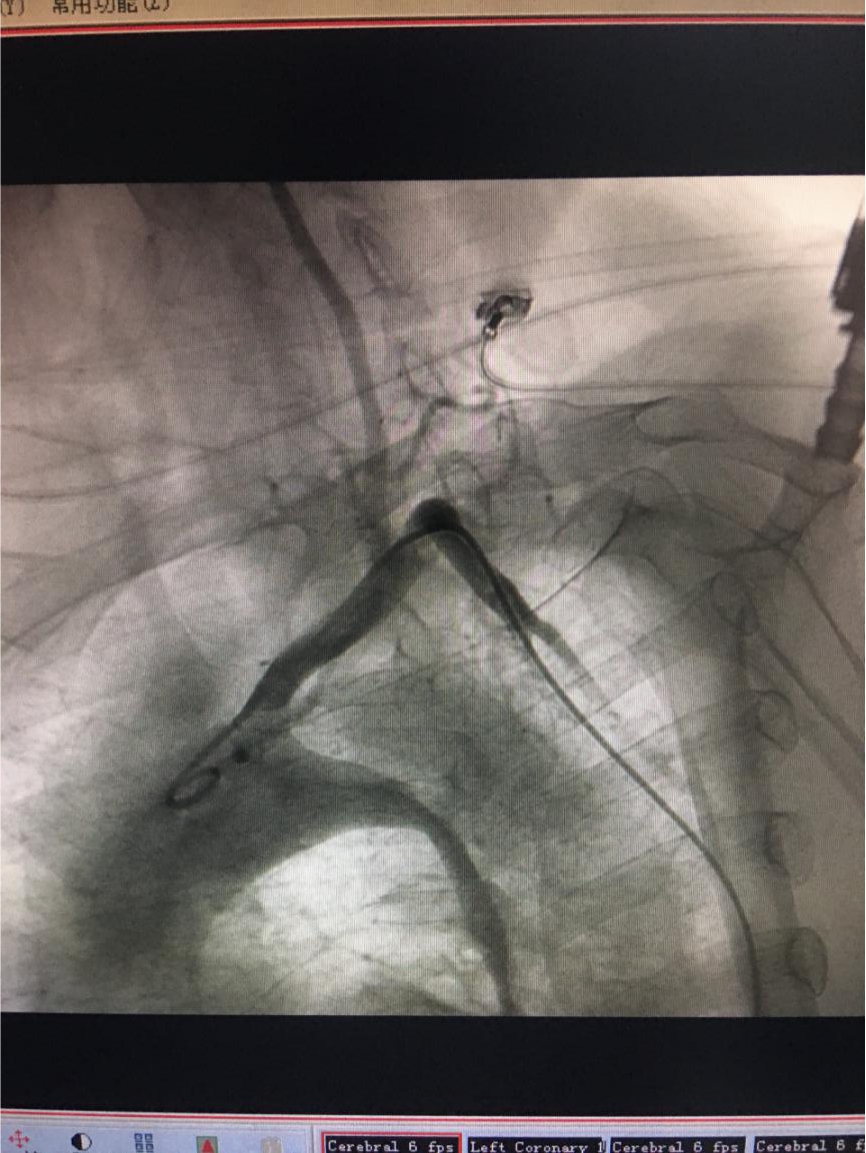

2、主动脉DSA检查:主动脉弓-降主动脉处见破裂口

3、主动脉夹层腔内隔绝术后